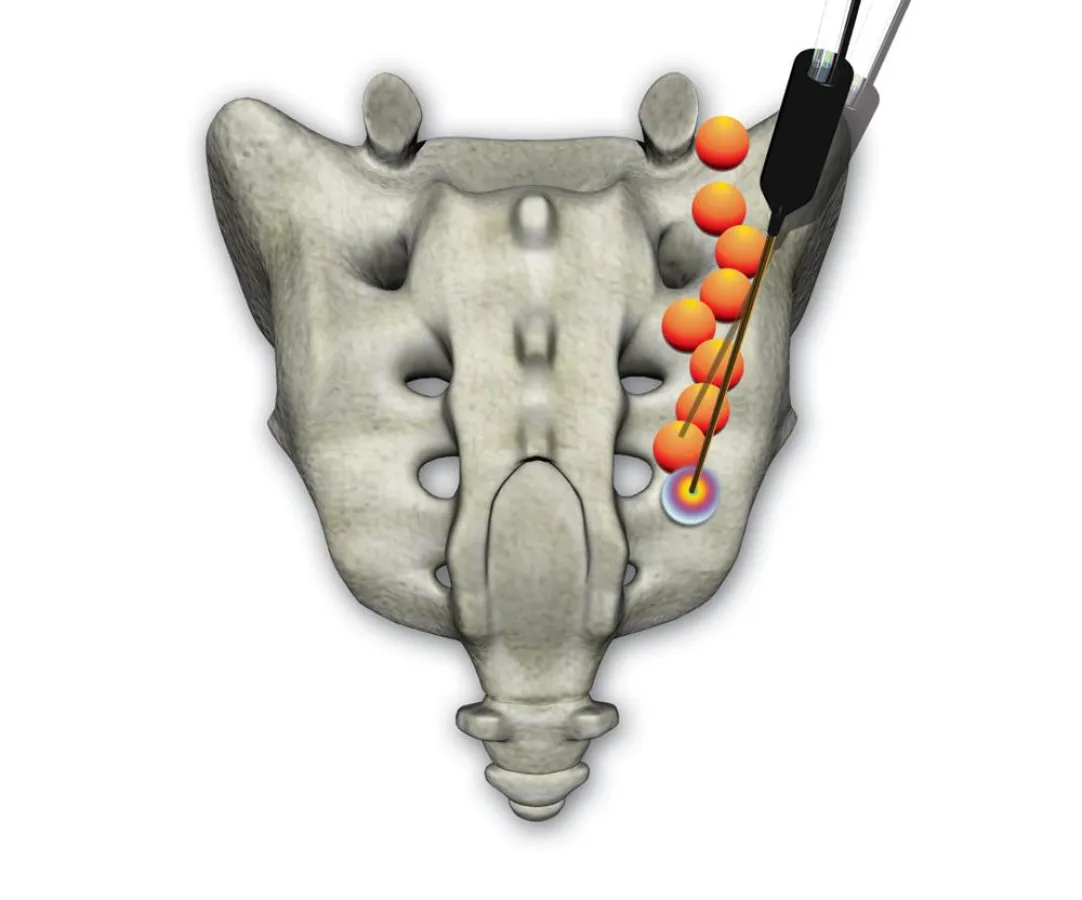

Der Eingriff erfolgt bei sterilen Bedingungen unter Röntgendurchleuchtung in örtlicher Betäubung, damit der Patient während der Behandlung ansprechbar ist und über seinen Schmerzzustand direkt Auskunft geben kann. Nachdem eine Führungskanüle exakt am Zielpunkt platziert wurde, schaltet ein lokales Betäubungsmittel den Nerv aus. Dann erzeugt die Sonde mittels Radiofrequenzen Wärme. Das Besondere ist die Form der Sonde, die eine kugelförmige Ausbreitung des Stroms ermöglicht und nacheinander mehrere Punkte, so genannte Läsionen, setzt. Dieser Vorgang kann solange wiederholt werden, bis das gewünschte Ergebnis erzielt ist. Die Risiken sind weitaus geringer als bei einer herkömmlichen Operation. Durch die konstante visuelle Kontrolle, die Wasserkühlung und die Ansprechbarkeit des Patienten ist eine Verletzung der umliegenden Nerven, Gefäße und Weichteile nahezu ausgeschlossen. Die Einstichstelle für die Sonde ist so minimal, dass sie lediglich steril mit einem Pflaster abgedeckt wird und eine Naht überflüssig ist.

Die Radiofrequenz-Neurotomie lässt sich auch bei Patienten mit tiefen Kreuzschmerzen, wie bei Beschwerden am Iliosakralgelenk oder der Lendenwirbelsäule anwenden. Sofern eine konservative Therapie keine Entlastung bringt, hilft hier die perkutane Denervierung, also die Behandlung durch die Haut mittels der speziellen Sonde.